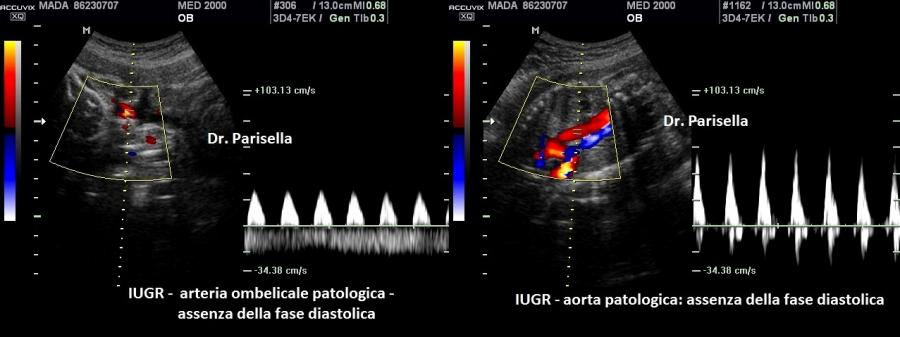

- il tipo II caratterizzata da una placenta piccola, IUGR, set cromosomico aggiunto di origine materna (diginia), micrognazia, anomalie del SNC (idrocefalia), cardiopatie, igroma cistico, oligoamnios.